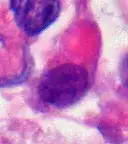

Rhabdoid Tumor Cell - 400X Magnification

The tumor histopathology is jumbled small and large cells. The tissue of this tumor contains many different types of cells including the rhabdoid cells, large spindled cells, epithelial and mesenchymal cells, and areas resembling primitive neuroectodermal tumor (PNET). As much as 70% of the tumor may be made up of PNET-like cells. Ultrastructure characteristic whorls of intermediate filaments are seen in the rhabdoid tumors (as with rhabdoid tumors in any area of the body). Ho and associates found sickle-shaped embracing cells, previously unreported, in all of 11 cases of AT/RT.[24]

Examination of the cerebrospinal fluid is important (CSF), as one-third of patients will have intracranial dissemination with involvement of the CSF. Large tumor cells, eccentricity of the nuclei, and prominent nucleoli are consistent findings.[29] Usually only a minority of AT/RT biopsies have rhabdoid cells, making diagnosis more difficult. Increasingly it is recommended that a genetic analysis be performed on the brain tumor, especially to find if a deletion in the INI1/hSNF5 gene is involved (appears to account for over 80% of the cases). The correct diagnosis of the tumor is critical to any protocol. Studies have shown that 8% to over 50% of AT/RT tumors are diagnosed incorrectly.